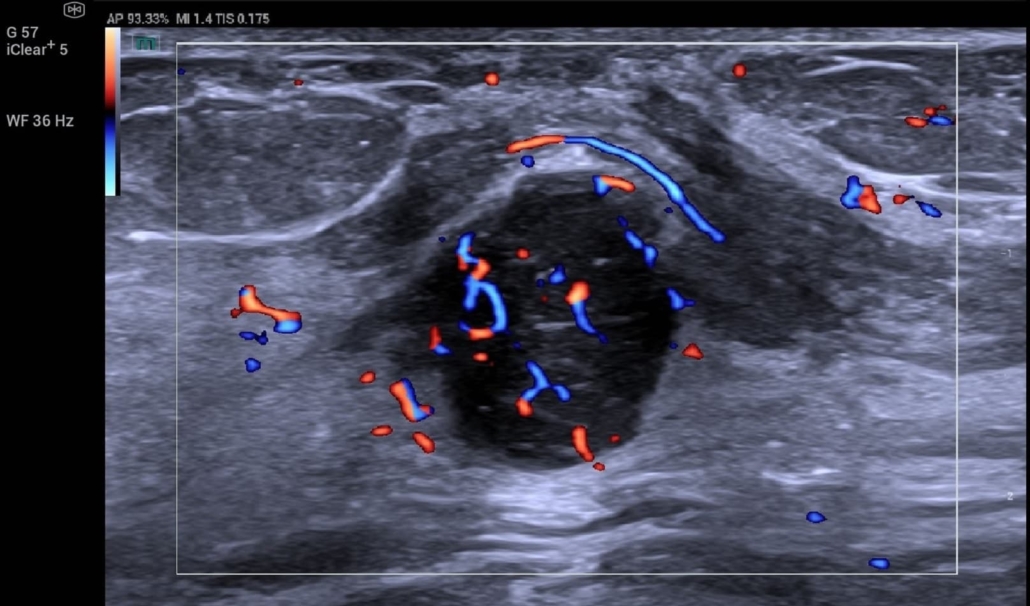

Ultrasound of breast carcinoma with Mindray’s new Resona A20

- Ultra micro angiography delivering highly sensitive detection of slow blood flow

- Super-resolution imaging capturing up to 500 frames per second

“The A20 gives us the opportunity for super resolution,” he explained. “Five hundred frames a second means a very, very high resolution, and a lot of dynamic information, additional information for the tumour which doesn’t exist or can be missed in conventional contrast examination.”